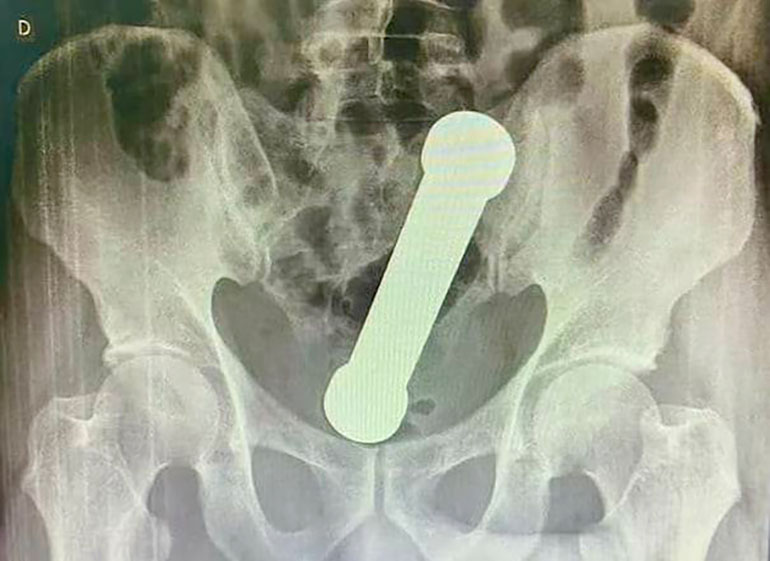

Au Brésil, un homme de 53 ans adepte du DBSM a mis un haltère de 2 kilogrammes et 20 centimètres dans son anus. Il a passé deux jours avec l'haltère dans le cul, mais s’est rendu chez le médecin que lorsqu'il s'est rendu compte qu'il ne pouvait plus chier et qu'il ressentait des nausées avec des douleurs abdominales. Un homme se coince un haltère de 2 kilos Après un examen clinique de la région rectale du patient, le personnel médical ne trouvait pas d’explication à ses maux. C’est grâce à une radio que les médecins ont compris ce qui gênait le coquin honteux. Un homme se coince un haltère de 2 kilos